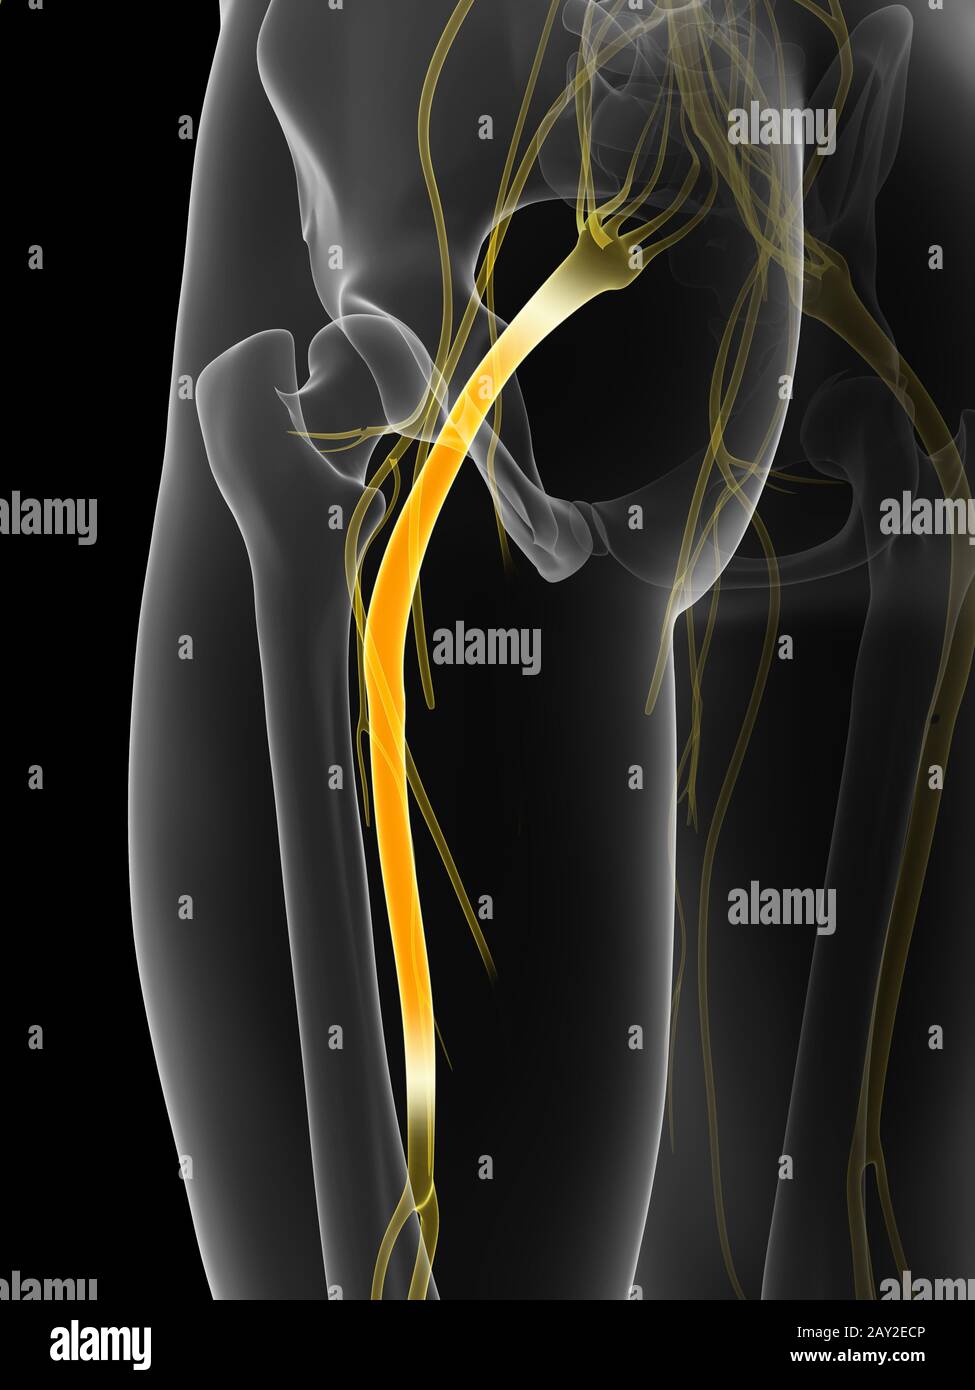

Rendu 3d illustration - nerf sciatique Banque D'Imageshttps://www.alamyimages.fr/image-license-details/?v=1https://www.alamyimages.fr/rendu-3d-illustration-nerf-sciatique-image343648003.html

Rendu 3d illustration - nerf sciatique Banque D'Imageshttps://www.alamyimages.fr/image-license-details/?v=1https://www.alamyimages.fr/rendu-3d-illustration-nerf-sciatique-image343648003.htmlRM2AY2EEY–Rendu 3d illustration - nerf sciatique